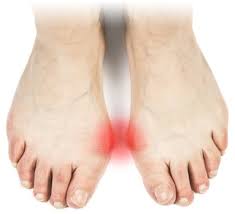

무지외반증 증상은 어느날 갑자기 나타나지는 않습니다. 발가락에 변형이 생기며 서서히 통증이 느껴지게 되는데요 저는 처음에는 그저 많이 걸었거나 오늘 신발이 좀 불편해서라고 생각하며 집에 돌아와 대충 주물러주고 족욕 하는 정도로 방치하였습니다.

하지만 지속적으로 하이힐과 구두를 신으면 점점 통증의 빈도가 심해지고 어떤 날은 걷다가 갑자기 쥐가 나기도 하면서 도저히 그대로 서있거나 걸을 수 없는 통증이 오게 되어 개선이 필요하다는 것을 인식하게 되었습니다. 처음에는 엄지발 쪽 발바닥이 찌릿찌릿했고 발바닥이 피가 안 통하는 느낌으로 발이 불편하며 나중에는 엄지발 옆의 튀어나온 부분이 욱신욱신하며 그 어떤 신발을 신어도 아프고 걷는 게 힘들기도 하였습니다.